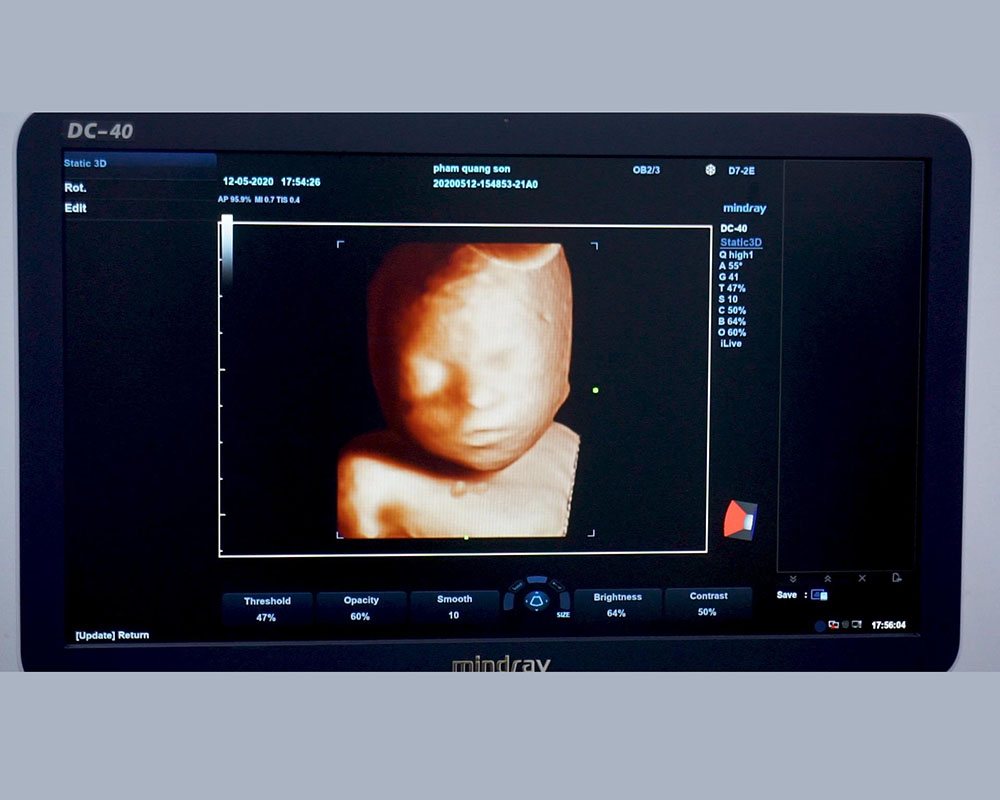

Hình ảnh 3D trên đầu dò khối D7-2E (Siêu âm trên mô hình thai)